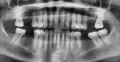

Мне 15 лет, у меня почему-то шатается нижний коренной зуб! Подскажите, пожалуйста, из-за чего он может шататься?!